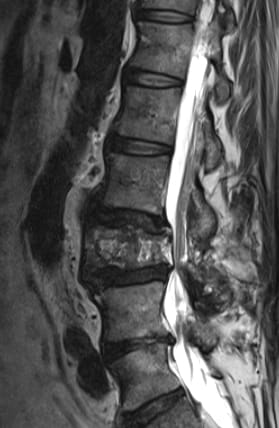

Stenose des Spinalkanals durch Destruktion des 3. Lendenwirbels (Morbus Paget) und Bandscheibenprotrusion L4/5. Zusätzliche Einengung des Spinalkanals durch knöcherne Anbauten an den Wirbelbögen und Gelenkfacetten.

Verschleißerscheinungen an der Wirbelsäule stimulieren die Selbstheilungskräfte in unserem Körper. Der Körper reagiert mit dem Anbau von Knochengewebe, welches die Wirbel untereinander stützen und stabilisieren soll. Häufig führen diese Knochenanbauten zu einer Arthrose der Facettengelenke sowie Verengungen des Spinalkanals und der Nervenöffnungen (Foramina). Die Folge sind starke Rückenschmerzen (Lumbago), Bewegungseinschränkungen und ausstrahlende Schmerzen ( Lumbo-Ischialgie), welche unter Umständen zu Lähmungserscheinungen führen können. Man spricht – wie bei der durch gefäßbedingte Durchblutungsstörungen verursachten «Schaufensterkrankheit» – von einer «Claudicatio spinalis».

Liegen neurologische Ausfallserscheinungen vor, z.B. Lähmungen, Schmerzen, Missempfindungen oder Einschränkungen der Gehstrecke, sollte eine operative Entlastung des Spinalkanals (Dekompression) erfolgen. Bei diesem Eingriff kann es erforderlich sein, je nach Intensität der Knochenanbauten, diese zu entfernen. Die Entfernung dieser Knochenanbauten kann zu einer Instabilität der betroffenen Wirbelsegmente führen. Liegt eine Instabilität vor, sollte diese stabilisiert werden. Eine Stabilisierung kann durch starre innere Abstützvorrichtungen ( fixateur interne) vorgenommen werden, was jedoch das Auftreten von Anschlusserkrankungen beschleunigen kann, oder durch dynamische Fixationssysteme erfolgen (z.B. Dynesis, CoFlex, DSS, Spine-shape). Der Vorteil einer dynamischen Stabilisierung liegt in der Erhaltung oder Wiederherstellung der Beweglichkeit und Funktion der Wirbelsäule.